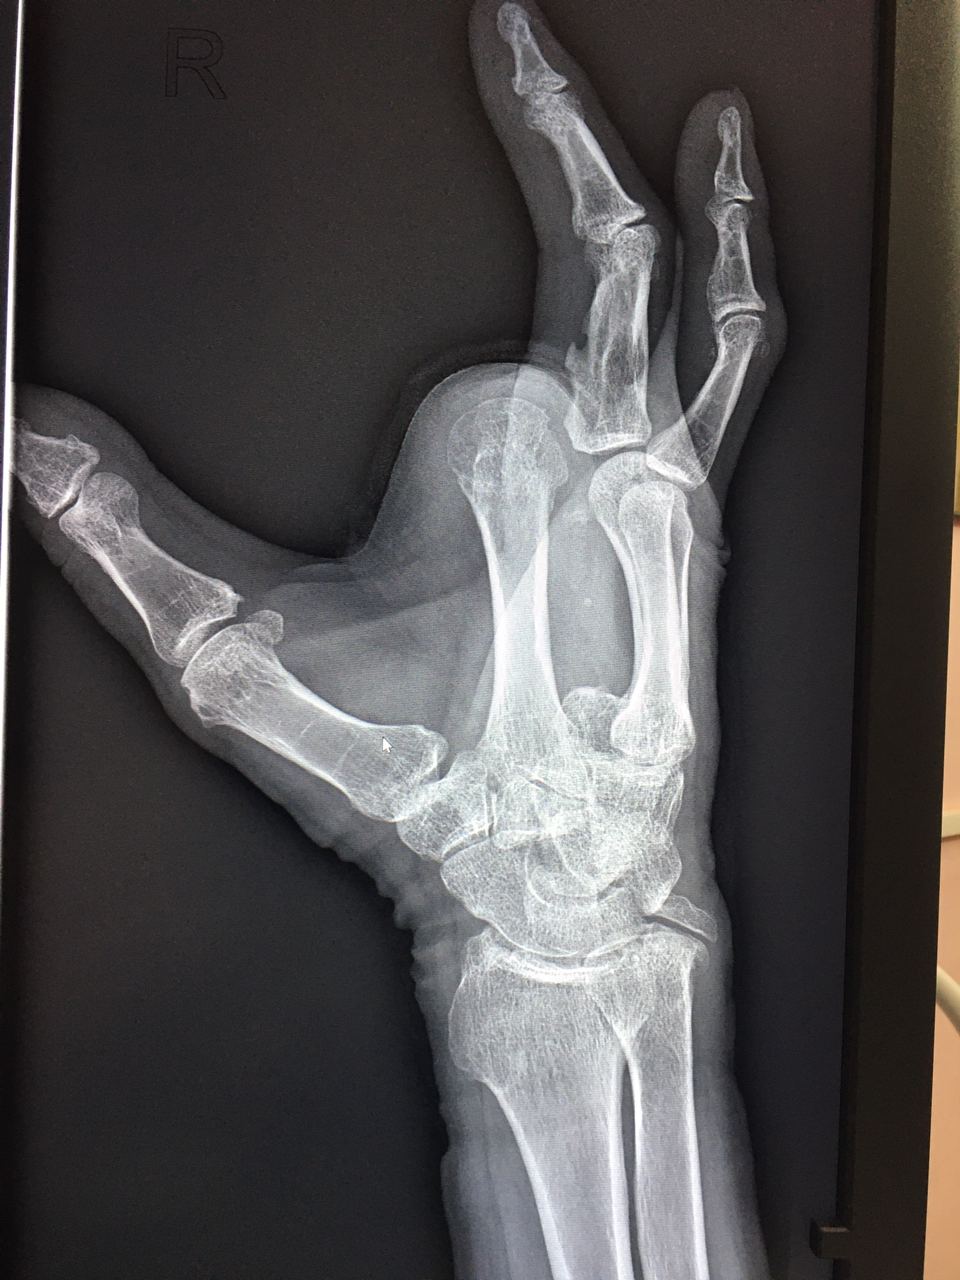

Травма от болгарки около двух недель назад. Архива нет( сейчас жалобы на боли, пациент сказал там «гниет все». Что можно сказать тут?

Без костно-деструктивных изменений.

Культя таких то пальцев на таком то уровне. Увеличен объем мягких тканей. Видимых костно-деструктивных изменений нет